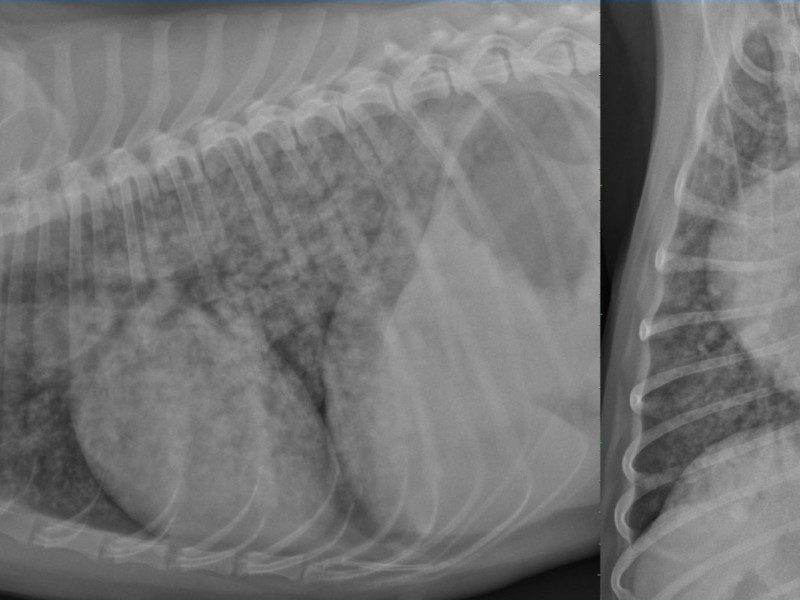

Radiographic examination of the thorax in right lateral and ventrodorsal projections.

We notice a severe diffuse peribronchic opacification of the lung. No other radiographic abnormality detected.

Given the anamnesis, these radiographic signs are consistent with a uremic pneumonia, which is an uncommon complication of pyometra. It is linked to the acute renal failure and belongs to the group of “non-cardiogenic edema” or “acute respiratory distress syndrome”. The lung field should regain its normal radiographic appearance when the renal failure is stopped. The common pitfall with this uremic pneumonia is to misunderstand that the peribronchic opacification corresponds to micro-nodules and metastatic disease.